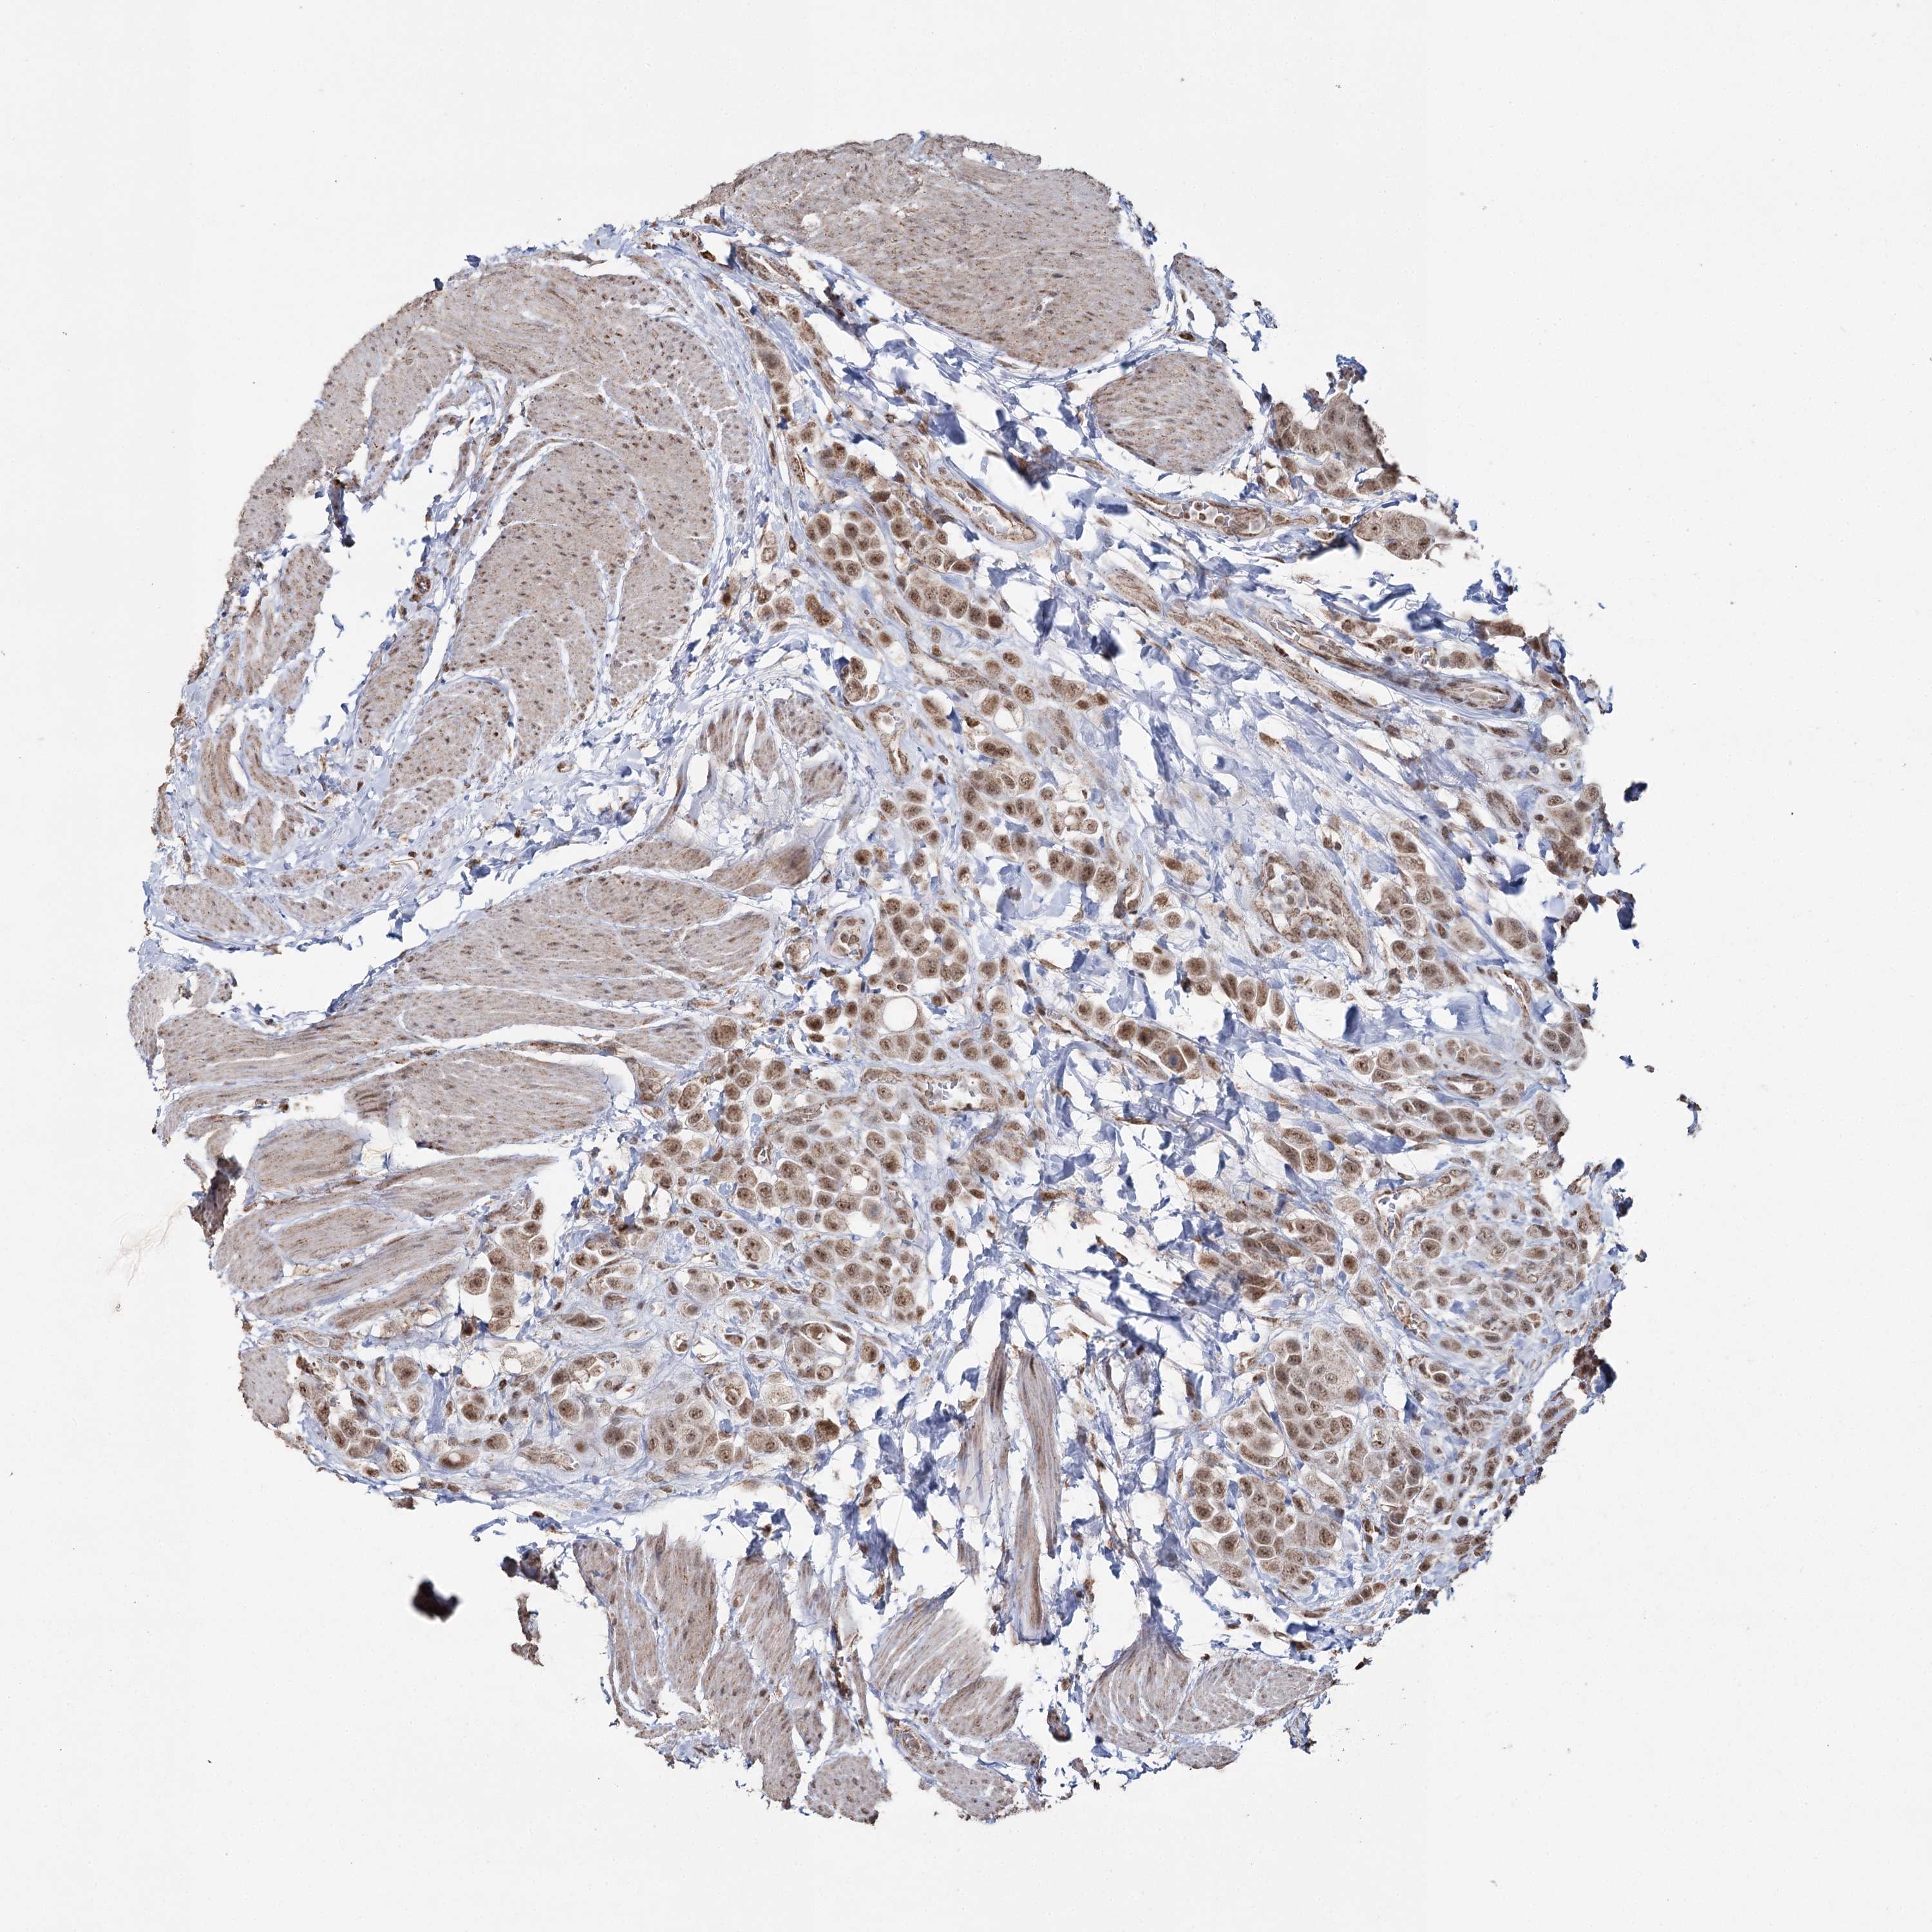

UROTHELIAL CANCER - Protein expressioni

A mouse-over function shows sample information and annotation data. Click on an image to view it in a full screen mode. Samples can be filtered based on level of antibody staining by selecting one or several of the following categories: high, medium, low and not detected. The assay and annotation is described here.

Antibody stainingi

Antibody staining in the annotated cell types in the current human tissue is reported as not detected, low, medium, or high, based on conventional immunohistochemistry profiling in selected tissues. This score is based on the combination of the staining intensity and fraction of stained cells.

Each image is clickable and will lead to virtual microscopy that enables deeper exploration of all samples and also displays staining intensity scores, fraction scores and subcellular localization as well as patient and tissue information for each sample.

Antibody HPA038484

Antibody HPA038485

Staining

High

Medium

Low

Not detected

Intensity

Strong

Moderate

Weak

Negative

Quantity

>75%

75%-25%

<25%

None

Location

Nuclear

Cytoplasmic/membranous

Cytoplasmic/membranous,nuclear

Urothelial carcinoma, High grade

Urothelial carcinoma, Low grade

Urothelial carcinoma, NOS